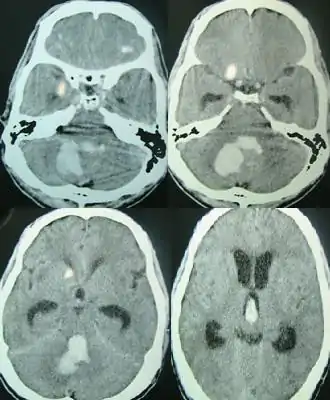

Hemorragia cerebral

Una hemorragia cerebral (también, hemorragia intracerebral, ICH) es un subtipo de hemorragia intracraneal producida en el cerebro. Puede deberse a un trauma cerebral o a un accidente. Se trata de una hemorragia intra-axial, es decir, una que se produce dentro del tejido cerebral[1] y no fuera de él. La otra categoría de hemorragia intracraneal es la de las hemorragias extra-axiales: por ejemplo, el hematoma epidural, el hematoma subdural y la hemorragia subaracnoidea, que ocurren dentro de la cabeza pero fuera del tejido cerebral.[cita requerida]